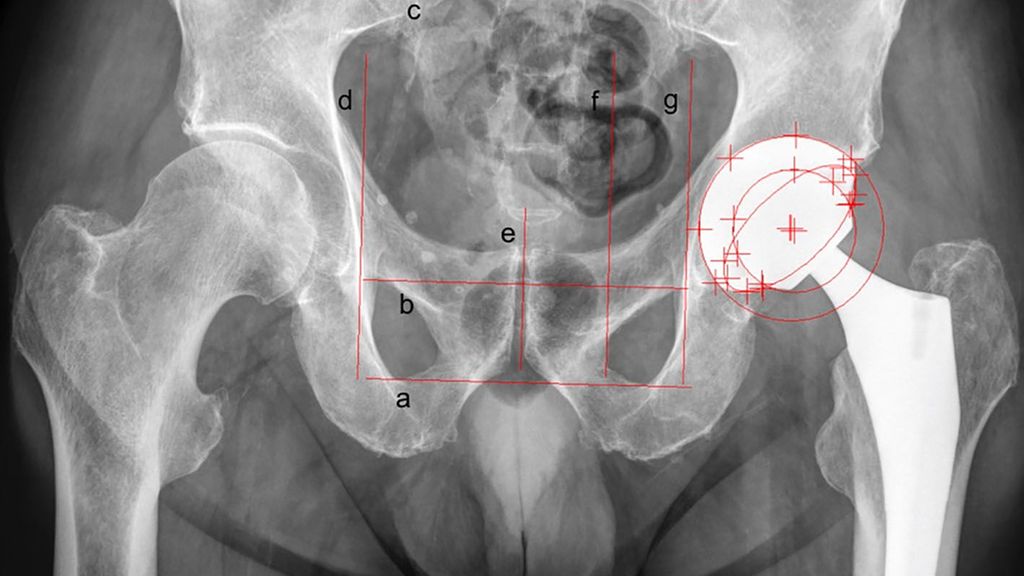

EBRA-Cup ermöglicht es, die Migration der Pfanne sowohl in Längs- (Kranial-/Kaudalwanderung) als auch in Querrichtung (Medial-/Lateralwanderung) zu messen.10 Hierzu werden je drei Tangenten in horizontaler und vertikaler Ausrichtung an bestimmte knöcherne Strukturen des Beckens im Röntgenbild angelegt (Abb.1). Während sich die Basislinie dabei an den Foramina obturatoria oder den kaudalen Konturen des Beckens (Tuber ischiadicum) orientiert, kann die mittlere horizontale Linie tangential am oberen Rand des Os pubis oder alternativ an den Foramina obturatoria eingezeichnet werden. Die obere Tangente soll einem der Foramina sacralia aufliegen. Im Gegensatz hierzu werden die beiden lateralen vertikalen Tangenten an den Foramina obturatoria oder am äußersten Punkt der jeweiligen Linea iliopectinea angelegt. Zuletzt markiert die vertikale Foramenlinie die Seite der zu vermessenden Pfanne. Eine weitere kürzere vertikale Linie kennzeichnet die Symphyse (Symphysenlinie).

Abb. 1: Migrationsanalyse der Pfanne mit EBRA-Cup im Standard-Hüftübersichtsröntgen: a) Basislinie, b) mittlere Linie, c) obere Linie, d) linke Linie, e) Symphysenlinie, f) Foramenlinie, g) rechte Linie